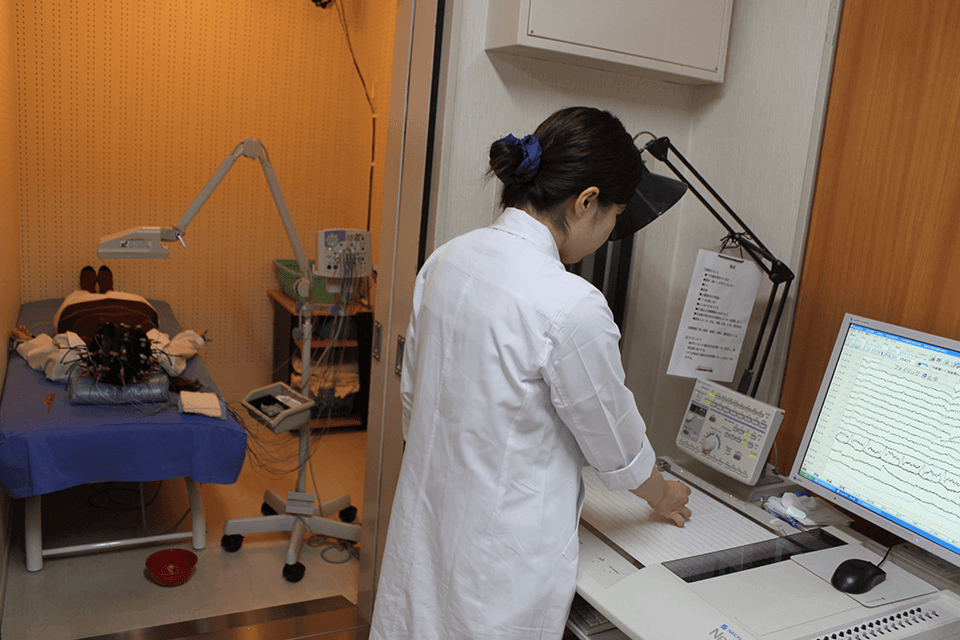

頭皮上に約20個の電極をつけ、脳の神経細胞から生じる微弱な電気信号を波形として記録する検査です。

異常を検出しやすくするため、検査の途中で眼の開閉・光の点滅・過呼吸による刺激を行い、脳の反応を見ます。

てんかん、意識障害、脳炎、代謝性脳症などの診断に役立ちます。